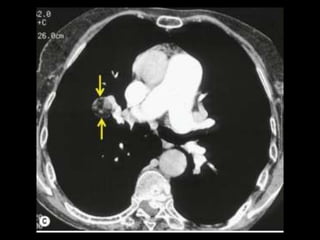

Embolia Pulmonar

Diagnóstico de embolia aguda na TC com contraste

é baseado na visualização direta de falhas de

enchimento parciais ou completas dentro das

artérias pulmonares;

Sinal da “rosca”;

Sinal do “trilho de trem”;

Outro sinal útil: formação de ângulos agudos com a

parede vascular, a perda completa da opacificação e

o aumento do diâmetro do vaso acometido.

Embolia Pulmonar Tumoral

Manifestação incomum das neoplasias;

Diagnóstico de êmbolo tumoral é difícil em bases

clínicas e pelos estudos radiográficos convencionais;

TC: dilatação multifocal múltipla e no aspecto de

“contas de rosário” nas artérias pulmonares

periféricas, primariamente com distribuição

subsegmentar;

Uma causa vascular do padrão “árvore em

brotamento” foi descrita em um paciente com

angiopatia trombótica tumoral pulmonar.